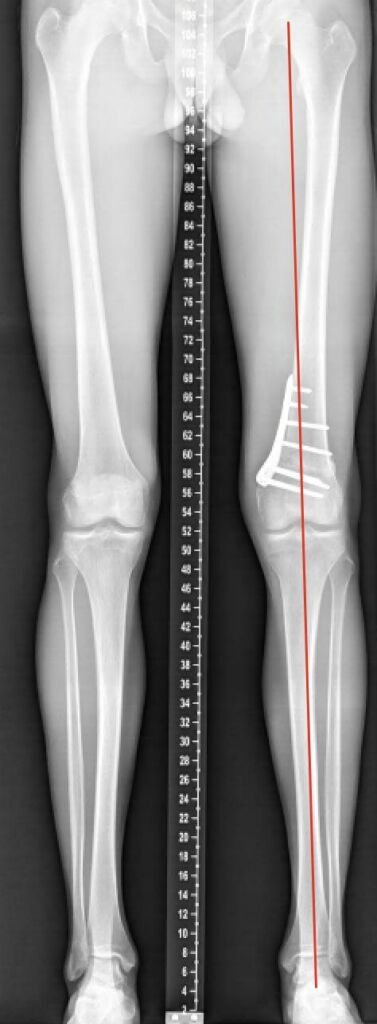

Valgus

Post-operatieve foto na een gesloten wig femur osteotomie.

Het bot wordt ook hier ingezaagd tot het scharnier (1), maar in plaats van het maken van een opening wordt er nu een wig uitgehaald (2). De wig wordt gesloten en de correctie op zijn plek gehouden door de plaat (3).